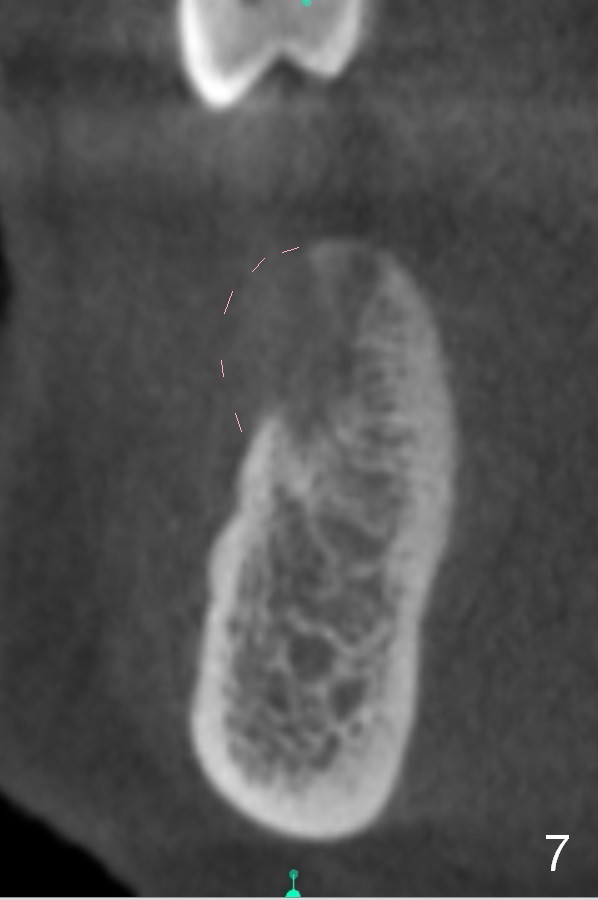

Chief complaint of a 69-year-old lady is "I cannot eat after bottom right bridge removal" (Fig.1). Exam reveals that the tooth #15 is also missing (Fig.2). Four implants are planned. CBCT shows low density of #31 socket (Fig.3,4, bone expanders) and the buccal coronal portion of the #29 socket (Fig.3,6,7, place implant as lingual as possible). The alveolus at the site of #30 is atrophic coronally (Fig.5). If insertion torque of individual implants is reasonably high, an immediate provisional bridge will be fabricated.